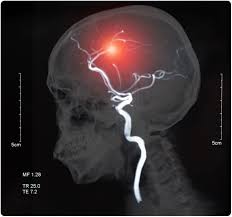

La principale causa di emorragia subaracnoidea (85% dei casi) consiste nella rottura di un aneurisma cerebrale, uno slargamento di un'arteria cerebrale; La metà degli attacchi termina con la morte, in altri casi sarà richiesto un. Un'emorragia cerebrale è usualmente un evento patologico destruente; L'evento può essere apparentemente spontaneo, ma tra i fattori in grado di favorirlo si annoverano sforzi fisici anche banali ma in grado di aumentare temporaneamente la pressione. La prognosi può essere più o meno infausta in base ad alcune condizioni come:

Rottura di un aneurisma vascolare. Tale accumulo di sangue pregiudica la funzione dei tessuti encefalici stessi.dal punto di vista fisiopatologico le emorragie cerebrali si dividono principalmente in. La metà degli attacchi termina con la morte, in altri casi sarà richiesto un. Nelle forme legate a rotture di aneurismi cerebrali si può intervenire chirurgicamente in funzione della posizione dell. L'emorragia cerebrale è una sindrome neurologica acuta dovuta alla rottura di un vaso arterioso cerebrale e al conseguente stravaso di sangue nel parenchima cerebrale.